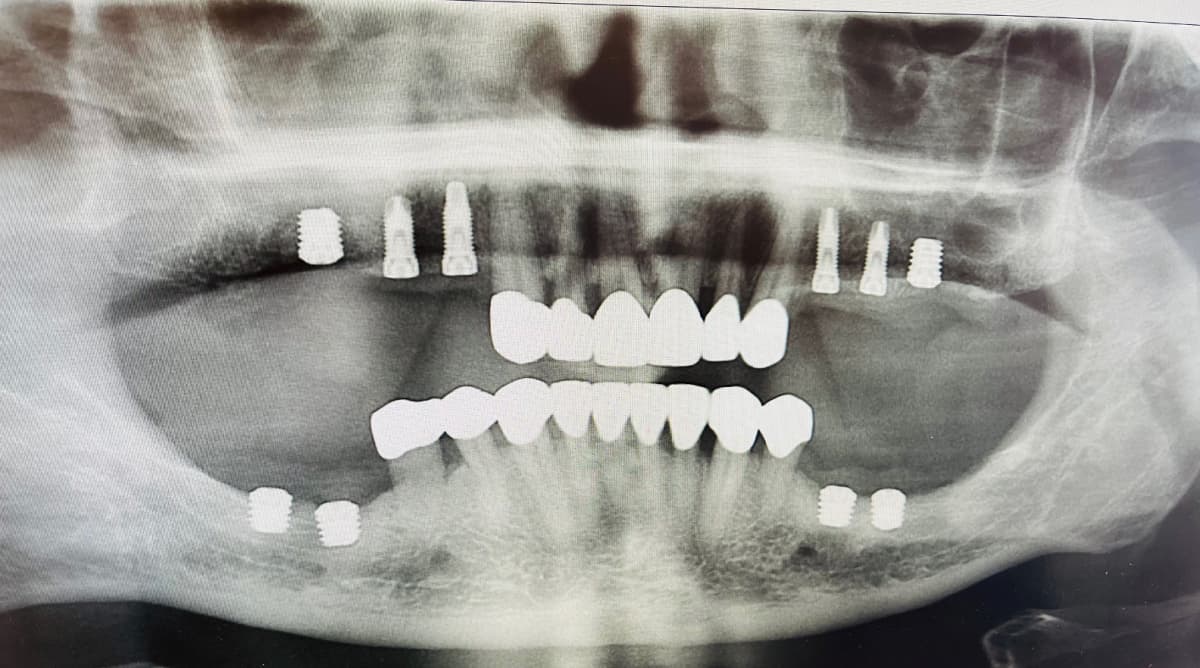

Un implant dentaire est une racine artificielle en titane insérée dans l'os de la mâchoire pour remplacer une dent manquante ou extraite. Le titane est un alliage biocompatible qui permet à l’os de se fusionner avec la surface implantaire, processus qu’on appelle l’ostéointégration. Un implant est conçu pour servir de support solide et durable à une prothèse dentaire telle qu'une couronne, un pont ou une prothèse dentaire complète.

Le processus commence par une consultation avec un de nos chirurgiens. Il évaluera l'état de votre santé bucco-dentaire, prendra des radiographies et discutera des options de traitements.